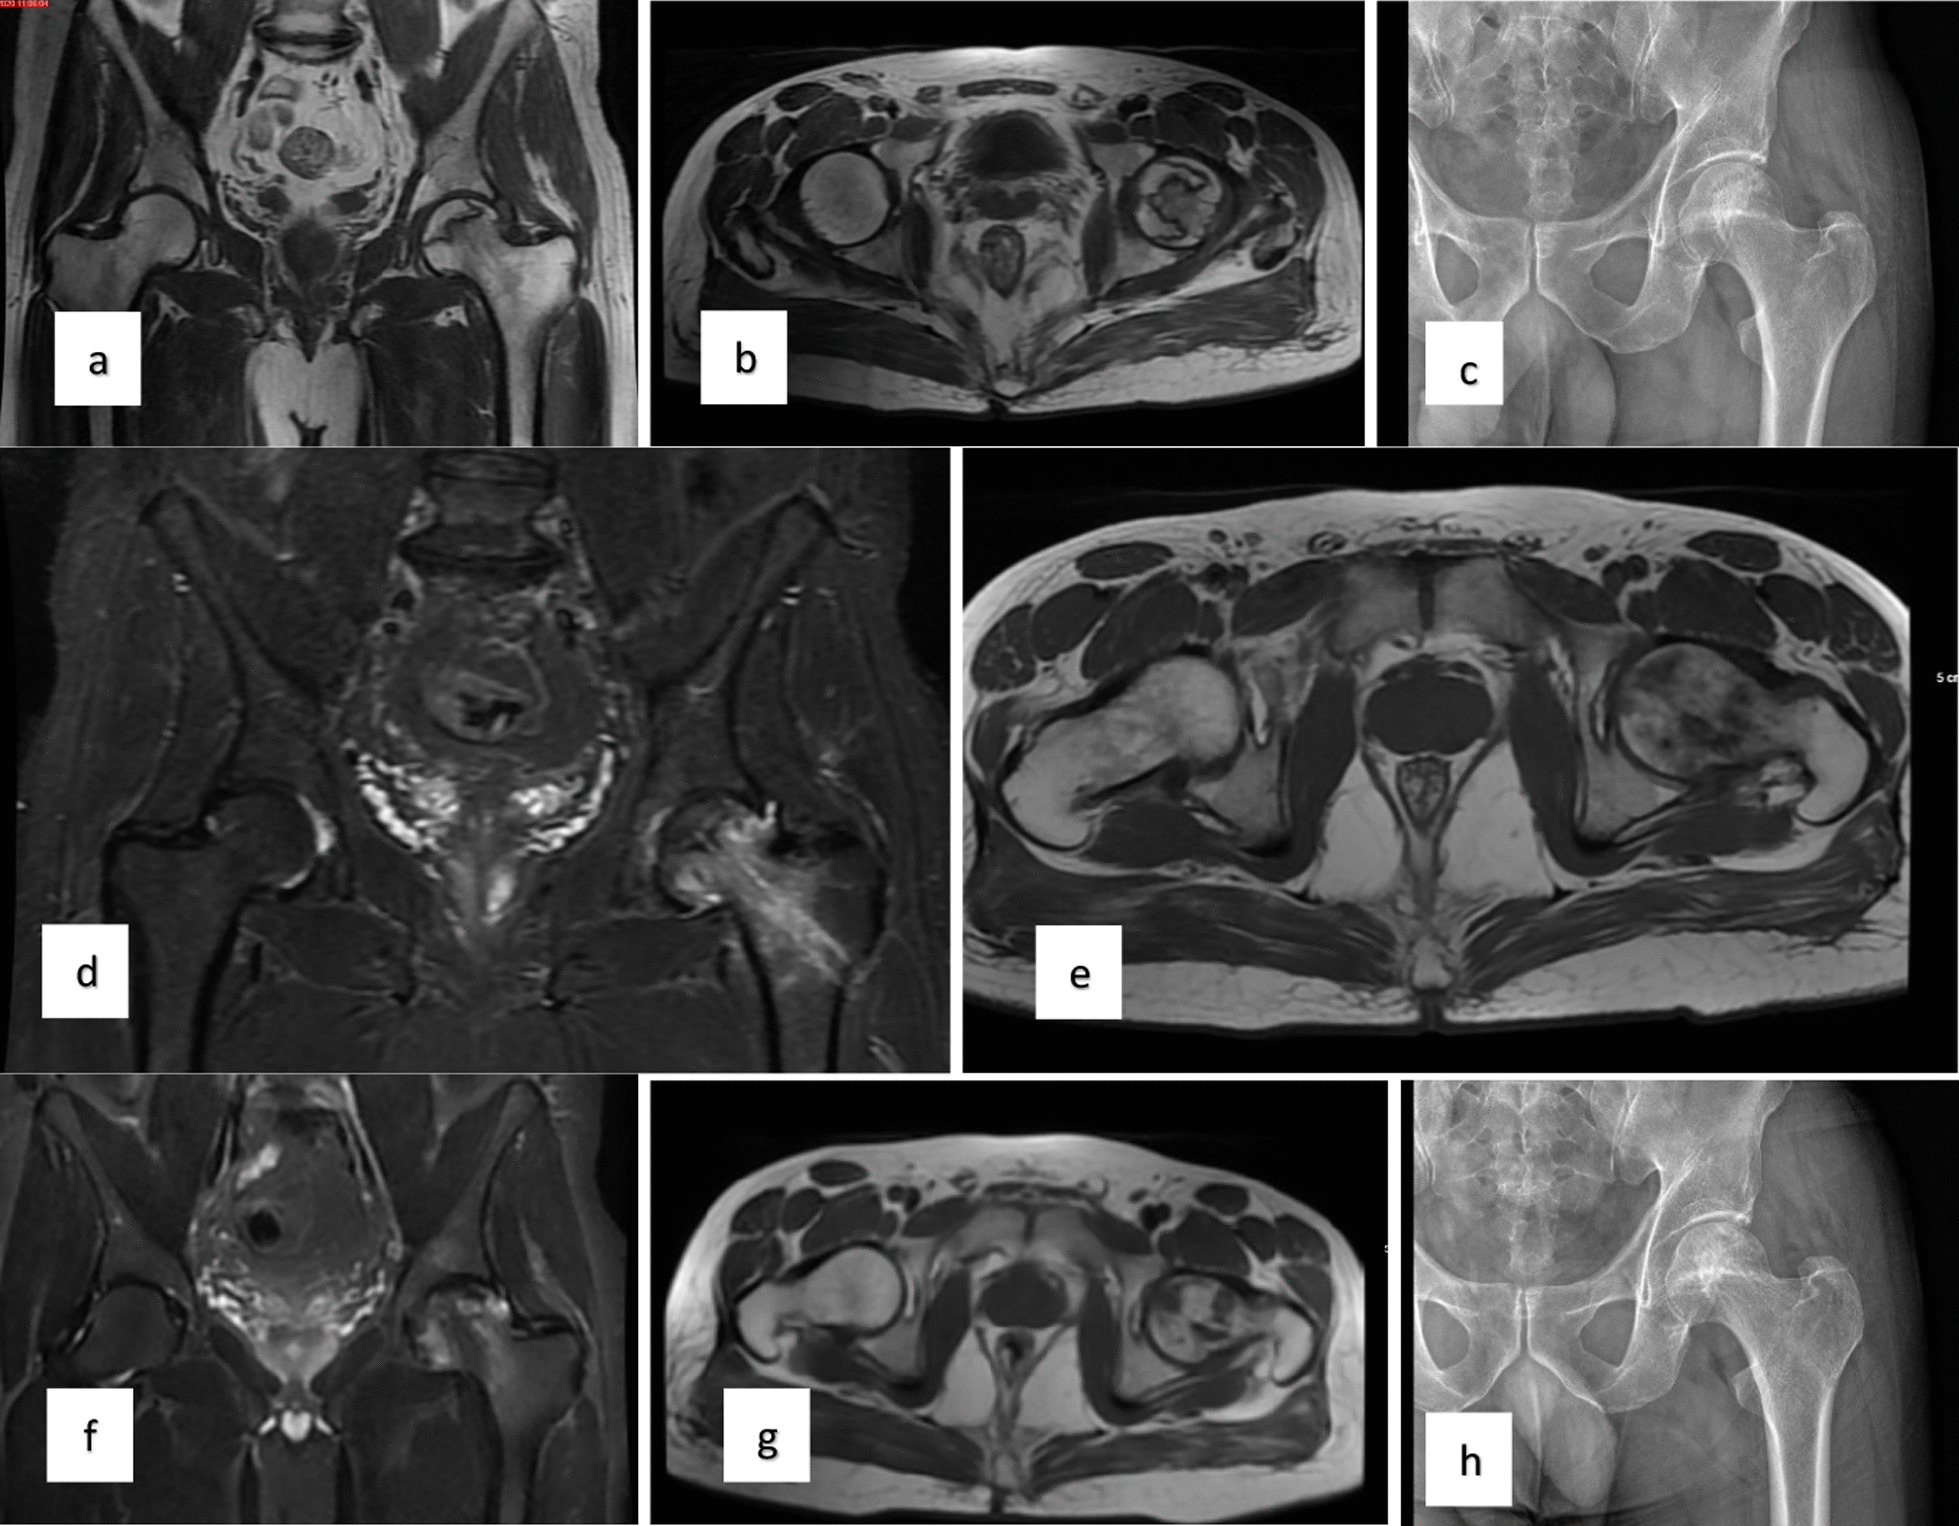

對患者的術前、3個月、6個月、1年和2年隨訪進行評估(圖1)。

當評估第1組和第2組的VAS評分時,得出結論:基線和第3個月的VAS評分相似;6、12、24個月時差異有統計學意義,第2組VAS評分明顯較低。比較各組患者的HHS時得出的結論是,基線評分相似,第2組在第24個月時有顯著改善。此外,兩組治療前后的HHS均顯著改善。第1組和第2組患者VAS評分變化見表1,HHS評分見表2(圖2)。